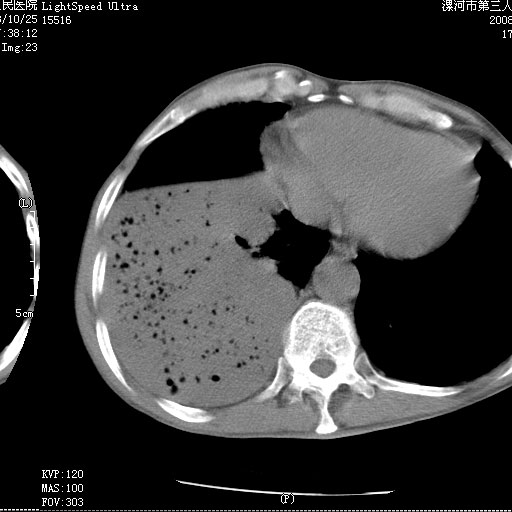

m 老年 发烧、呼吸困难,慢支、肺气肿多年;记的那次是下午大概17:38做的,晚上窒息死亡。

上面的层面就慢性支气管炎肺气肿、肺大泡,别的没有什么、也就不传了。

当时我怀疑:1、阻塞性肺不张早期 2、肺脓肿早期,望老师们发表意见

应该是脓胸的表现,右下肺气管阻塞考虑为痰栓.

你怀疑的有道理,慢支、肺气肿、肺打泡是有了,右下肺的病变有待商议;

首先考虑右下肺炎症并不张,不除外早期肺泡癌改变

病灶边缘清---多个含气小腔---近端未见通畅气管影-----支持-----慢性肺脓肿继发阻塞性肺不张

阻塞性肺不张原因-----脓液未排出

1、右侧脓胸;2、copd;

3、细支气管肺泡癌可以排除,病变以斜裂为界,呈大片状高密度影,内可见多发小气泡,表明有产气杆菌感染所致,内无明显的支气管“枯树枝征”表现,再结合其临床改变(细支气管肺泡癌临表表现重、影像表现轻)所以不符合细支气管肺泡癌(炎症型)的改变。

病变按肺叶分布,病变内可见多个小空腔影,未见充气支气管影,中间段支气管管腔肺窗示密度欠均匀,下肺支气管分叉处基底段支气管隐约可见,未见明显狭窄,中叶支气管通畅,

考虑:阻塞性肺炎伴小脓肿形成可能性大。(痰栓可能性大)

右下肺实变,内有弥漫分面小气泡而无支气管征,叶间裂前移,呈臌大之形,而无收缩之状,兼纵隔稍左行移,故。不支持不张,倒支持大叶肺叶,如楼上所说,小气泡不象残留之肺,不可以考虑产气菌感染吗。

阻塞性肺炎,肺脓肿形成。依据,右下支气管不通,大片实变形内可见小气泡。不支持肺不张。